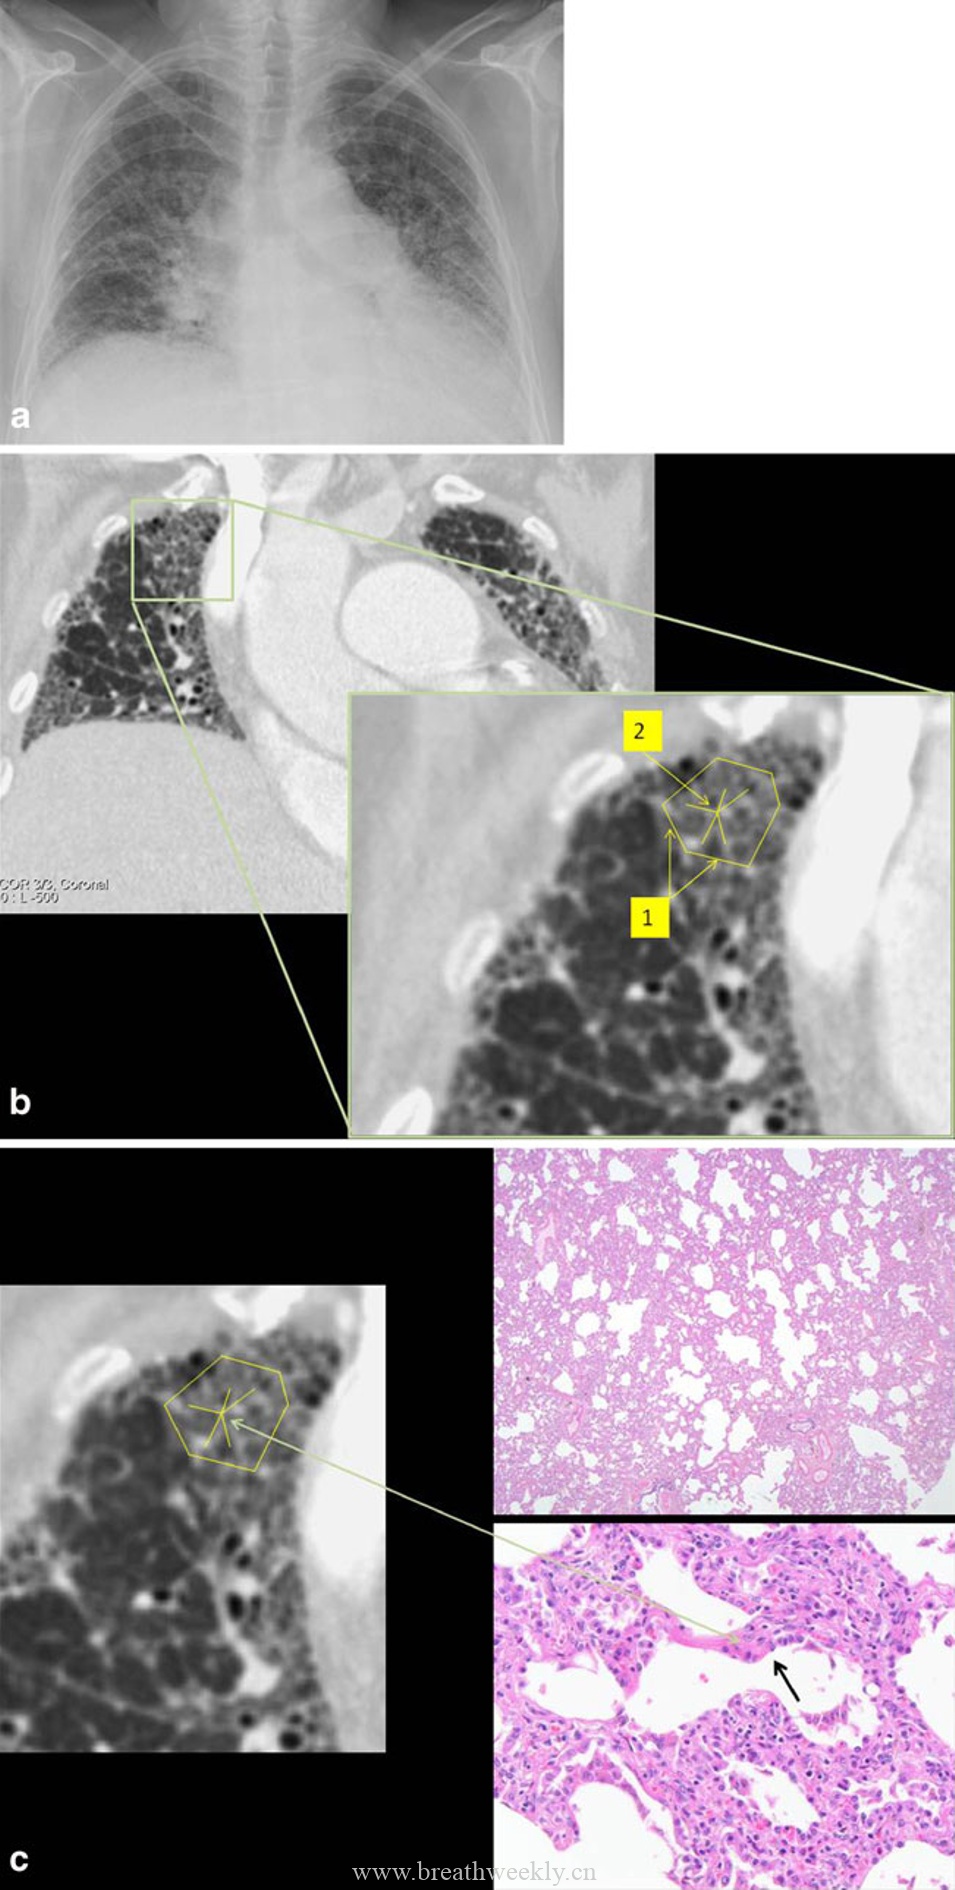

4. 非特异性间质性肺炎(NSIP)

典型表现:胸膜下对称分布,下叶为主。病理为均匀的间质炎症和纤维化。